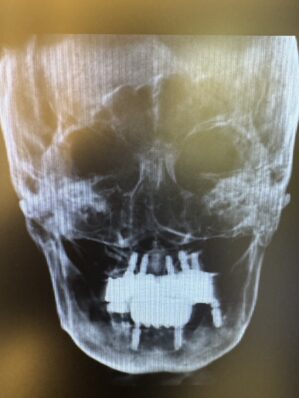

今回は10年以上前に行われた全顎のインプラントが弱ってしまいお痛みの主訴で来院された患者さん。

ザイゴマにてリカバリーを行う症例でした。上顎を4本のザイゴマインプラントで治す予定でしたが、ギリギリ前歯が使えたため上を5本、下顎を4本のインプラントを用いて即日で治療しました。

非常に難易度の高い症例でしたが2人で協力して無事に完了することができ安心しました。